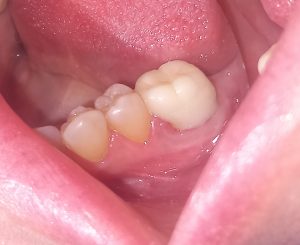

Αρχική εικόνα πριν τη διχοτόμηση του δοντιού

Τελική εικόνα μετά την ανασύσταση του δοντιού